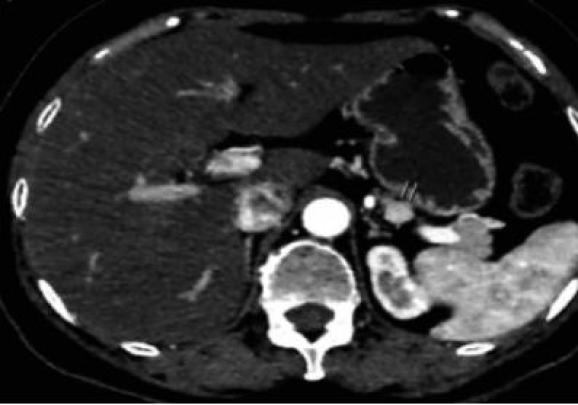

进一步完善实验室检查及影像学检查(表1,图1)后,我们依据2009年美国内分泌学会临床指南[2],从患者的症状、发作症状时的血糖、胰岛素、C肽、胰岛素原、β羟丁酸、使用胰高糖素后血糖上升的水平、以及是否使用降糖药物、胰岛素抗体等综合分析,修正诊断为:胰岛素瘤。该患者下一步治疗:评估手术条件,外科手术治疗。

01. 胰岛素瘤(Insulinoma)

约90%以上的胰岛素瘤为良性肿瘤,发生在胰头、体和尾部的各占1/3。肿瘤大多体积较小(82%<2cm,47%<1cm),不到10%的患者为恶性胰岛素瘤、多发性肿瘤,或为多发性内分泌腺瘤病1型[3]。胰岛素瘤具体定位的方法如下: